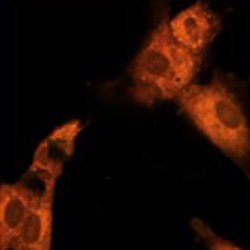

살아있는 세포

#세포 상태를 즉각적으로 확인

#줄기세포의 품질의 일관성 유지

#맞춤형 치료의 정밀도 향상